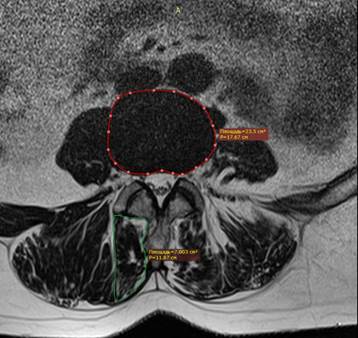

По данным МРТ были оценены качественные и количественные характеристики m. psoas, m. multifidus и m. erector spinae. Качественным параметром было содержание жира в мышце согласно классификации Goutallier [9]. Она включает 5 градаций: 0 – мышца без жира, I – жировые прожилки внутри мышцы, II – жира доля жира меньше, чем мышцы, III – количество жира сопоставимо с мышцей, IV – жира больше, чем мышцы. Количественной характеристикой была относительная площадь поперечного сечения мышцы (relative cross-sectional area). Она рассчитывалась как отношение площади поперечного сечения мышцы к площади межпозвонкового диска (рис. 1) [10].

Рис. 1. Измерение relative cross-sectional area m. multifidus пациентки Р. 61 года

Источник: составлено авторами по результатам данного исследования.